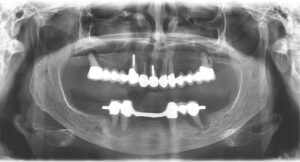

Hier sieht man das Problem:

Zerstörter Zahnhalteapparat – Das erste Röntgenbild zeigt die Situation eines Patienten mit schwerer Parodontitis. Die Zähne haben zum Teil keine knöcherne Verankerung. Auf der zweiten Abbildung ist zum besseren Verständnis der Knochenverlauf durch eine rote Linie dargestellt. Die grüne Linie stellt den normalen Knochenverlauf im gesunden Zustand dar. Die Fläche zwischen beiden Linien entspricht dem Knochenverlust.